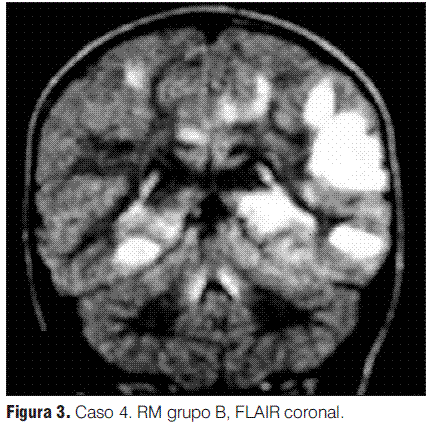

Se realizaron RM en la primera semana de evolución de la enfermedad en todos los pacientes, revelando en todos los casos alteraciones características (tabla 3).

Grupo A: EMDA a pequeñas placas, lesiones menores a 5 mm de diámetro.